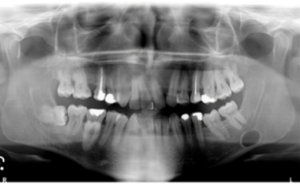

What is the best diagnosis for the pano below?

A

static bone cyst